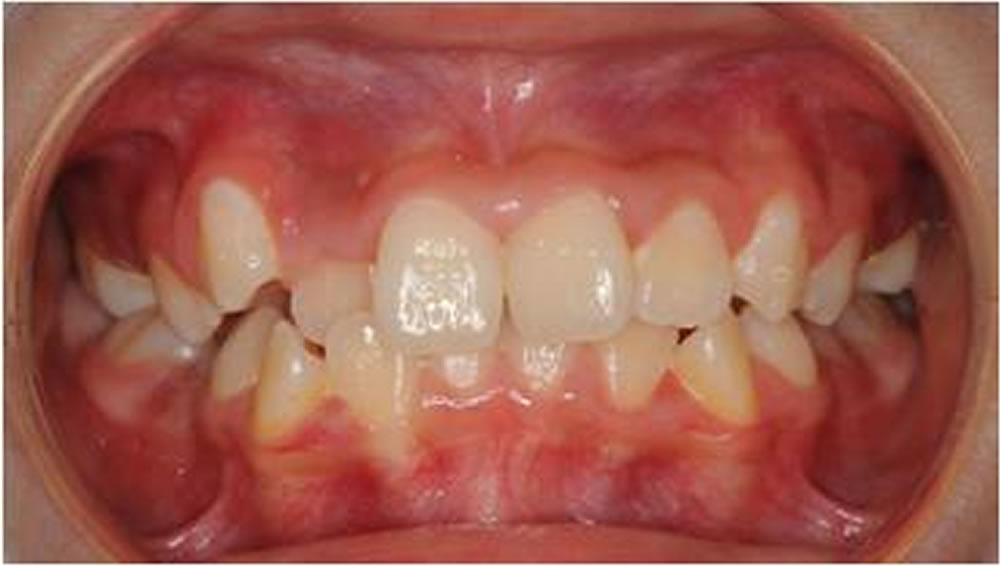

BiVi歯科・矯正歯科で実施した小児矯正の治療例をご紹介

▼当院で実際に行った小児矯正治療の症例をご紹介します。